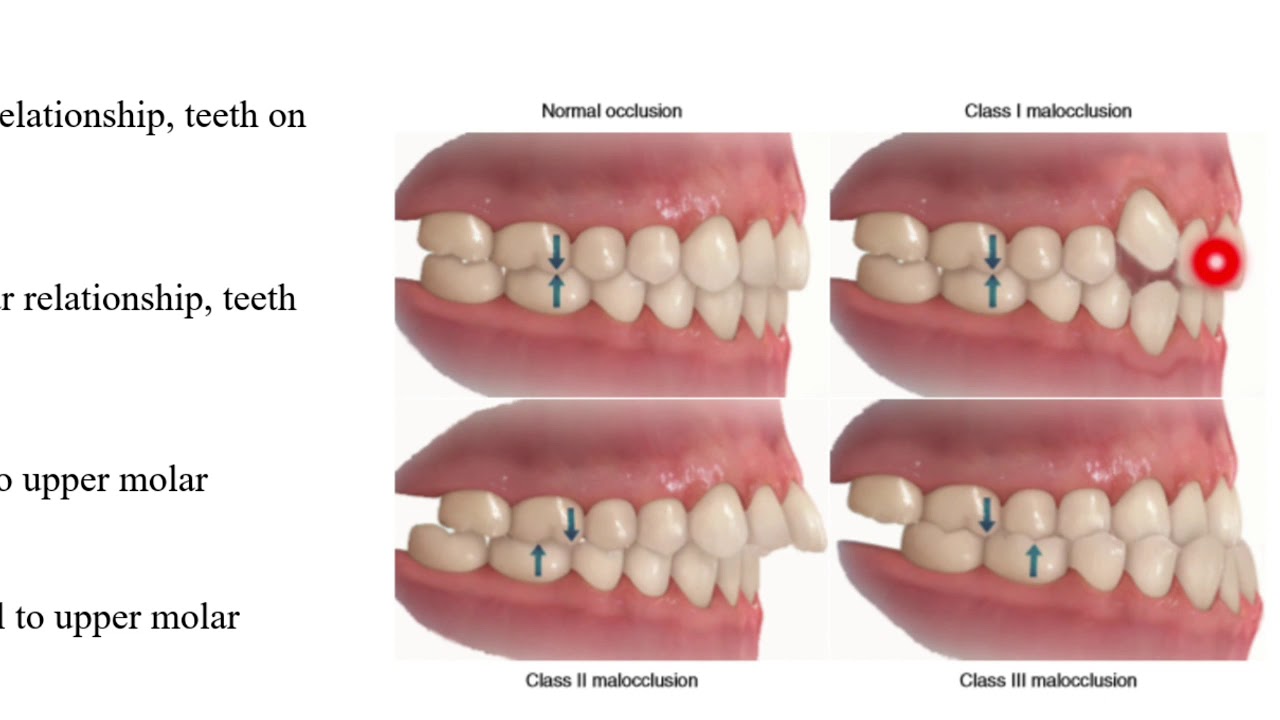

Malocclusion Class I Youtube Class i malocclusion with severe lower anterior crowding and increased overjet treated without extraction. Angle determined that class i malocclusions involve mild crowding and positional or rotational aberrations. class ii malocclusions include the upper incisors creating noticeable “overjet” (tilting outwards) and the upper incisors tilting labially (towards the lips). An overview of the case resulted in the damon ultima psl with variable torques utilized correcting the malocclusion with resolution of the significant crowding and lack of overbite along with substantial arch development. Despite this strong molar connection, patients with class i malocclusion may show additional dental anomalies, such as crowding, spacing, rotations, or misalignment of individual teeth . understanding how and when this malocclusion develops is important to comprehend its etiology.

Class I Crowding Youtube An overview of the case resulted in the damon ultima psl with variable torques utilized correcting the malocclusion with resolution of the significant crowding and lack of overbite along with substantial arch development. Despite this strong molar connection, patients with class i malocclusion may show additional dental anomalies, such as crowding, spacing, rotations, or misalignment of individual teeth . understanding how and when this malocclusion develops is important to comprehend its etiology. Crowding is an increasingly common type of malocclusion caused by a discrepancy in tooth jaw size that leads to twisted and misaligned teeth. two methods to treat this malalignment are tooth material reduction and arch width expansion. Class i malocclusions with severe crowding and tooth size discrepancies may be successfully treated orthodontically with extraction therapy, and co management with other specialists. correction of the discrepancies will optimize occlusal result (overjet, overbite, midline shift, and smile esthetics). Ackerman profitt system of classification involves steps to assess malocclusion. crowding, spacing, cross bite, open bite, deep bite, bimaxillary protrusion, rotations, and other dental problems are discussed, along with their causes and management options. Despite all this, treatment results do not always remain stable. the most common type of malocclusion in mixed dentition patients is crowding. it occurs when there is a discrep ancy between the size of the tooth mass and the size of the supporting bony bases. two treatment strategies used to correct this problem are extraction and expan sion.

Crowding Youtube Crowding is an increasingly common type of malocclusion caused by a discrepancy in tooth jaw size that leads to twisted and misaligned teeth. two methods to treat this malalignment are tooth material reduction and arch width expansion. Class i malocclusions with severe crowding and tooth size discrepancies may be successfully treated orthodontically with extraction therapy, and co management with other specialists. correction of the discrepancies will optimize occlusal result (overjet, overbite, midline shift, and smile esthetics). Ackerman profitt system of classification involves steps to assess malocclusion. crowding, spacing, cross bite, open bite, deep bite, bimaxillary protrusion, rotations, and other dental problems are discussed, along with their causes and management options. Despite all this, treatment results do not always remain stable. the most common type of malocclusion in mixed dentition patients is crowding. it occurs when there is a discrep ancy between the size of the tooth mass and the size of the supporting bony bases. two treatment strategies used to correct this problem are extraction and expan sion.

Class I Malocclusion Youtube Ackerman profitt system of classification involves steps to assess malocclusion. crowding, spacing, cross bite, open bite, deep bite, bimaxillary protrusion, rotations, and other dental problems are discussed, along with their causes and management options. Despite all this, treatment results do not always remain stable. the most common type of malocclusion in mixed dentition patients is crowding. it occurs when there is a discrep ancy between the size of the tooth mass and the size of the supporting bony bases. two treatment strategies used to correct this problem are extraction and expan sion.

Class Iii Malocclusion Youtube